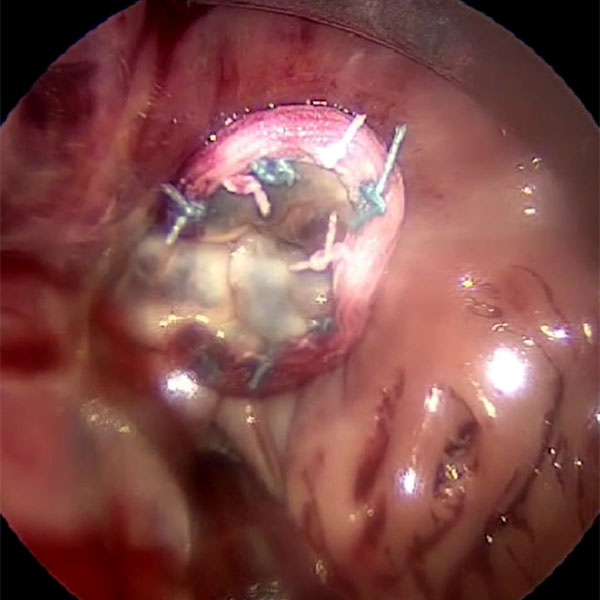

Minimally invasive mitral valve surgery is performed through a 4-5 cm incision in the patient's right chest without cutting open the sternum (breastbone). This technique can be used for: